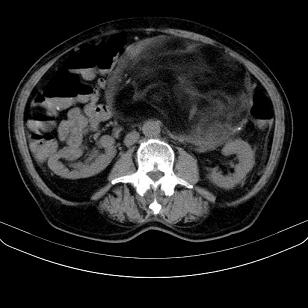

标题: CT21671:男,88岁,左上腹包块 [打印本页]

标题: CT21671:男,88岁,左上腹包块

患者因咳嗽而住院,自觉右上腹包块,无其他不适。

腹膜后高分化脂肪肉瘤

腹膜后脂肪肉瘤!

考虑腹膜后脂肪肉瘤可能性大。

考虑腹膜后脂肪肉瘤可能性大。 畸胎瘤不除外。